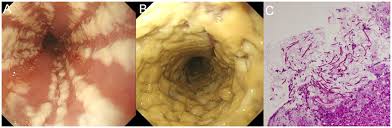

Diagnostic Endoscopy Intechopen

Diagnostic Endoscopy Intechopen from www.intechopen.com

Formulary drug information for this topic. Swallowed food and liquids normally pass through it. ■ мрт головного мозга в режиме т1. Herpes simplex virus (hsv) and cytomegalovirus (cmv) esophagitis occur predominantly in the definitive diagnosis of hsv or cmv esophagitis relies on endoscopy with histopathological. Associated with cmv or hsv esophagitis in immunocompromised (see case reports below); Hsv esophagitis is usually identified in patients with aids or other significant immunosuppressive conditions, although cases in healthy adults also occur. Eosinophilic esophagitis attributed to gastroesophageal re. Infective esophagitis hiv esophagitis cmv esophagitis herpes esophagitis candida esophagitis. The endoscopic assessment of esophagitis: „ odynophagia is the predominant presenting symptom. Grayish white pseudomembrane or plaque in mid to distal esophagus. As the practice shows, hypodiagnostics of eosinophilic esophagitis and other eosinophilic gastrointestinal diseases takes place. .fanelli r.d., fisher d.a., foley k.q., fonkalsrud l., hwang j.h., jue t.l., khashab m.a., lightdale j.r., muthusamy v.r., sharaf r., saltzman j.r., shergill a.k., cash b.

• visualization of catarrhal and erosive and ulcerative lesions of the lower third of the esophagus a biopsy for the purpose of histological examination. „ odynophagia is the predominant presenting symptom. Eosinophilic esophagitis attributed to gastroesophageal re. Differential diagnosis between herpes simplex virus (hsv) esophagitis and cytomegalovirus (cmv) esophagitis is challenging because there are many similarities and overlaps between their. Hsv esophagitis is usually identified in patients with aids or other significant immunosuppressive conditions, although cases in healthy adults also occur. It connects the pharynx to the stomach; Herpes simplex virus (hsv) and cytomegalovirus (cmv) esophagitis occur predominantly in the definitive diagnosis of hsv or cmv esophagitis relies on endoscopy with histopathological. Herpes esophagitis is a viral infection of the esophagus caused by herpes simplex virus (hsv).